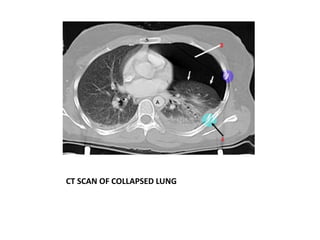

Pneumothorax can be spontaneous, caused by underlying lung conditions (secondary) or trauma/medical procedures (non-spontaneous). It is diagnosed through chest x-ray or ultrasound identifying air in the pleural space. Management includes needle aspiration for small pneumothoraces or chest tube insertion for larger ones. Further treatment may involve procedures like pleurodesis, abrasion, or surgery to prevent recurrence. Physiotherapy focuses on improving ventilation and clearing secretions through techniques like breathing exercises, positioning, and airway clearance.